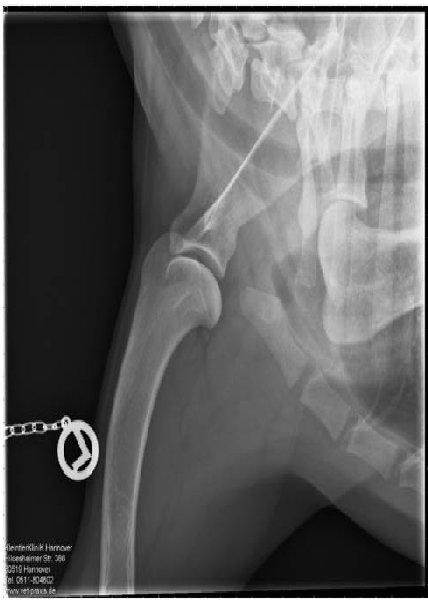

ED - OCD - Röntgenaufnahme